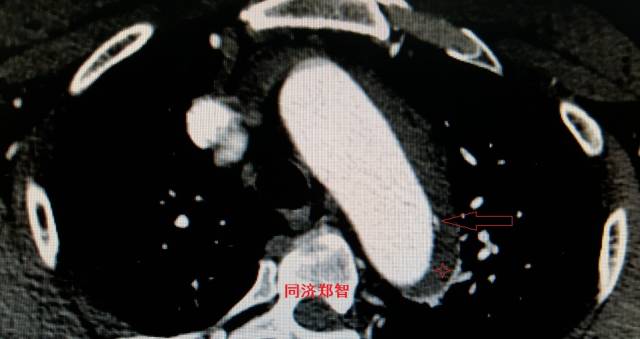

病例十二

平扫CT提示降主动脉一接近外周的钙化点(红色箭头所示),CTA证实为降主动脉壁间血肿。